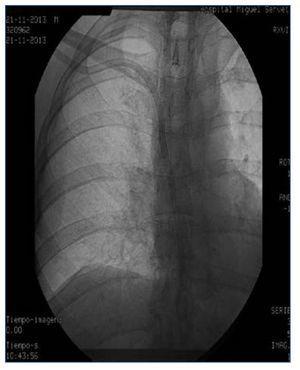

Presentamos el caso de una paciente en hemodiálisis, que había agotado todas las posibilidades de realización de FAVI y que se dializaba a través de catéter yugular tunelizado colocado en yugular interna derecha. Anteriormente había sido portadora de varios catéteres en vena yugular derecha e izquierda y en ambas femorales, habiendo desarrollado trombosis de estas como complicación asociada. Por malfuncionamiento del catéter yugular derecho se realiza cavografía, que muestra trombosis oclusiva de toda la vena cava superior con gran hipertrofia de la vena ácigos (figura 1). Se intenta abordaje por vía yugular derecha, que es imposible debido a su trombosis, por lo que se realiza abordaje subclavio derecho y se consigue implantar el catéter dejando el extremo distal próximo al cayado de la ácigos (figura 2). La paciente se dializó a través de este catéter sin incidencias, con flujos de 300-350 ml/min consiguiéndose un KTV medio de 1,64 durante 4 meses, momento en que fue sometida a un trasplante renal de donante cadáver. La colocación de catéteres en la vena ácigos está descrita en numerosas ocasiones como complicación del procedimiento en el abordaje de accesos vasculares subclavios o yugulares. Sin embargo, con nuestro caso mostramos que la vena ácigos puede ser una alternativa válida como acceso venoso central funcionante, con buenos flujos y buena calidad de diálisis en pacientes con trombosis en los territorios venosos habituales.

Figura 1.